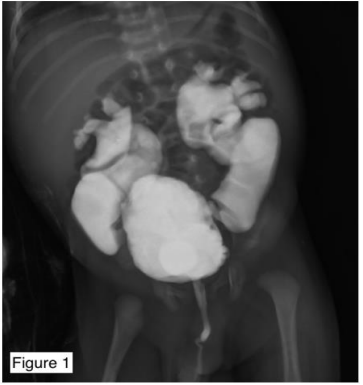

Figure 1: a Micturating Urethrogram showing bilateral grossly dilated ureter and renal pelvis along with posterior urethral valve as a narrowing in the posterior urethra.

Posterior urethral valves (P.U.V.s), also referred to as congenital obstructing posterior urethral membranes (C.O.P.U.M.) is a congenital malformation affecting males where the membranous folds of the urogenital membrane obstruct the membranous and prostatic urethra. It is a congenital disorder only seen in males, with an incidence of 1 per 4000 to 1 per 25000 live births in some areas. Type 1 P.U.V. results from the abnormal insertion and absorption of the distal Wolffian duct during the development of the bladder. Type 3 PUV is observed as a membrane in the posterior urethra, originating from the incomplete canalisation between the anterior and the posterior urethra. Type 2 P.U.V. is now considered a normal anatomical variant. Regardless of the type, P.U.V.s present with urinary tract obstruction, bladder distension, abdominal distension, difficulty voiding, poor stream of urine, recurrent Urinary Tract Infection (U.T.I.), diurnal enuresis and a failure to thrive. They are diagnosed Antenatally by Ultrasonography showing distended or thick-walled bladder, bilateral hydroureters, and bilateral hydronephrosis. However, the gold standard for the diagnosis is a Micturating CystoUrethrogram (MCU), also known as a Voiding Cystourethrogram (V.C.U.) shows dilation/elongation of the posterior urethra during voiding along with signs of vesicoureteral reflux if present. This patient was antenatally diagnosed with posterior urethral valves at seven months of fetal age and came to us for further management. Antenatal diagnosis of Posterior Urethral Valves on Ultrasonogram involves visualisation of 1. Keyhole sign- due to the distension of the urethral proximal to the valves and a distended bladder, 2. marked distention or hypertrophy of the bladder, 3. Hydronephrosis and hydroureter. An Ultrasonogram of the abdomen and pelvis done postnatally revealed bilateral gross hydroureteronephrosis, which was missed on antenatal scans. The baby was born to a G2P1L1 mother and weighed 3.04kg at birth. The baby cried immediately after birth and maintained oxygen saturation at 100% on room air. The patient was managed with Cystoscopy with Posterior Urethral Valve fulguration with circumcision.